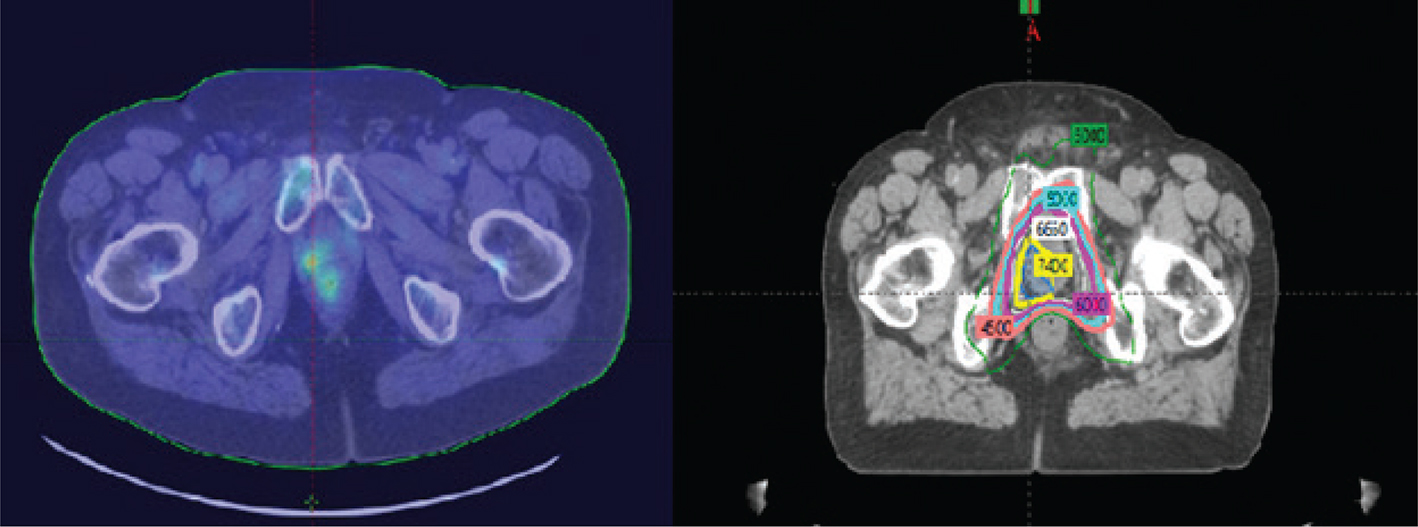

Process improvements in radiation oncology have demonstrated outstanding progress in the care of prostate cancer patients. Volumetric planning has provided security in radiation therapy target definition and modern imaging tools including multi-parametric magnetic resonance imaging. New metabolic agents used for positron emission tomography have provided more confidence that tumor targets are well defined and treated with accuracy (24). Intensity modulation has permitted radiation oncologists to place sharper dose gradients across normal tissue structures, including bladder and rectum, with increased dose to tumor target, permitting higher dose to tumor targets with no additional clinical morbidity. This has served to expand our role in prostate cancer to treat early metastatic disease with success (3, 5, 6). Decreased dose and sharper dose gradients to normal tissue, aided by intensity modulation, decrease radiotoxicity to the rectum, small bowel, bone structures including the acetabulum, and bladder (Figure 1).

Fig 1

Figure 1. Process improvements in radiotherapy of prostate cancer. A, Dose gradients across bladder and rectum for a traditional radiation therapy using intensity modulation. Daily image guidance allows for adjustments in positioning each day relative to target motion. B, A cone beam computer tomography image obtained pre-therapy to validate target positioning on a daily basis. The security provided by image guidance permits titration in planning target volumes which in turn decrease dose to normal tissue further. The use of volume modulated arcs permits rapid therapy delivery over a few minutes giving confidence to both physicians and patients in limiting intrafraction motion of targets further promoting security in daily treatment execution. C, Arc geometries applied to prostate cancer care. Optical tracking provides both stability and security in daily positioning and monitors external motion during therapy. D, An example of optical tracking in a prostate cancer patient. Image courtesy of the Department of Radiation Oncology, UMass Chan Medical School and UMass Memorial Health.